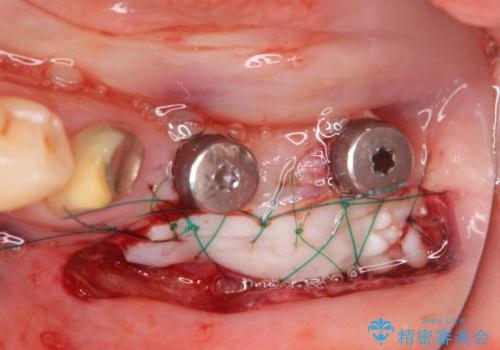

抜歯後、インプラントを用いて咬合機能を回復すると共に周囲に強固な角化歯肉を移植することによりより長期にわたり安定したインプラント周囲環境となるよう治療を計画します。

インプラント周囲の角化歯肉が存在することにより、歯ブラシがしやすくなりインプラントにトラブルが起きる確率を減らしより長期的な予後を望むことができます。